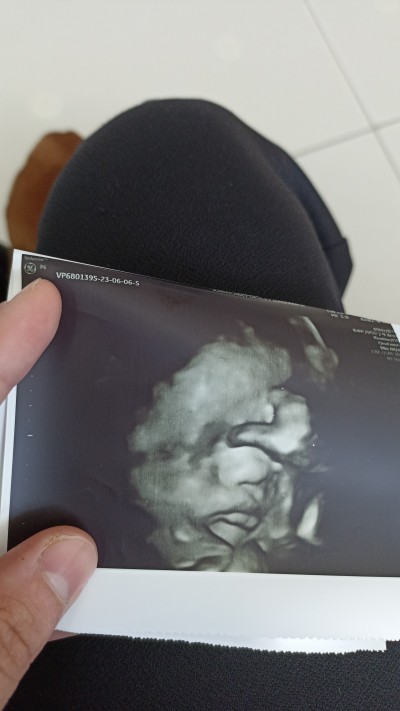

Selam kızlar dün kanamam oldu acile gittik her şey yolundaydı bugün gittik gördük 32+0 kilosu 1886

Oy dudaklara kurban olsun teyzesi maşallah maşallah nazar değmesin tosuna

Anammm bal dudakk<3

Maşallah sağ Salim dogsun inşallah bizim buradaki devlet hastanelerinde perinatoloji bölümü yok onu da geçtim detaylı ultrason yapılacak bir cihaz da yok o yüzden böyle net göremiyorum bir kere özele gittim orada gördüm keşke bir daha görebilsem çok tatlı oluyor insanın daha çok heyecanlandırıyor bu şekilde net yüzünü görebilmek

Hele dudaklara bak maşallah Rabbım sağlıkla kucağına almayı nasip etsin canım

Ultrason fotosunun sevimli oldugunu da ilk defa gördüm :) gecmiş olsun

Anam elini yüzüne koymuş kız ay yerim ben onu balım Allah'ım banada nasip et bir kız inşallah

Sıpa seni sıpa elinide alnına koymuş anneyi korkutma teysezinin balı:D yerim o burnunu bak maşallah sana maşallah

Burun baba dudak ben  ♥